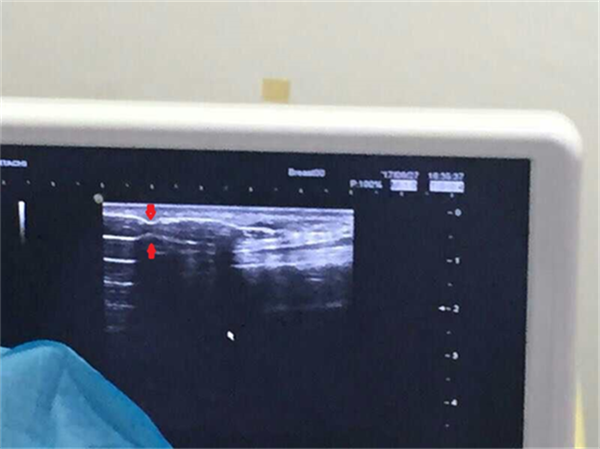

治疗前B超下内瘘血管可见明显狭窄(双凹切迹,红色箭头处)